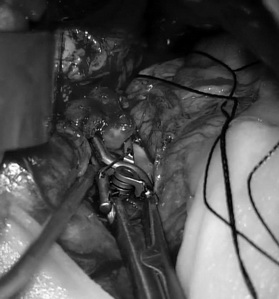

经科室讨论,神经外六科吴杰主任团队为解先生实施了手术,术中将动脉瘤与周围血管准确分离,并成功夹闭。术后复查CT,显示动脉瘤被夹闭,手术区域未见明显异常。

神经外六科吴杰主任介绍:动脉瘤的手术是在脑组织之间的自然间隙分离脑组织,从血管外暴露动脉瘤,用一种特制的夹子夹闭瘤颈(动脉瘤泡和脑血管连接的部位),这样脑血管中的血流就不会再进入动脉瘤,从而达到治疗目的。这种方法历史悠久,随着显微神经外科手术技术的提高,疗效也在不断的进步。优点是如果动脉瘤夹闭完全,则复发率很低,对于合并有颅内较大血肿的患者也很合适,夹闭动脉瘤的同时可以进行血肿清除。